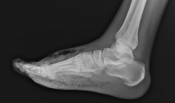

What’s the diagnosis? Gepost op 11 december 2019 door netwerkvsseh What’s the diagnosis? By Dr. Katie Selman @emdaily.cooperhealth.org Dit delen: Delen op X (Opent in een nieuw venster) X Share op Facebook (Opent in een nieuw venster) Facebook Delen op LinkedIn (Opent in een nieuw venster) LinkedIn E-mail een link naar een vriend (Opent in een nieuw venster) E-mail Afdrukken (Opent in een nieuw venster) Print Vind-ik-leuk Aan het laden... Gerelateerd